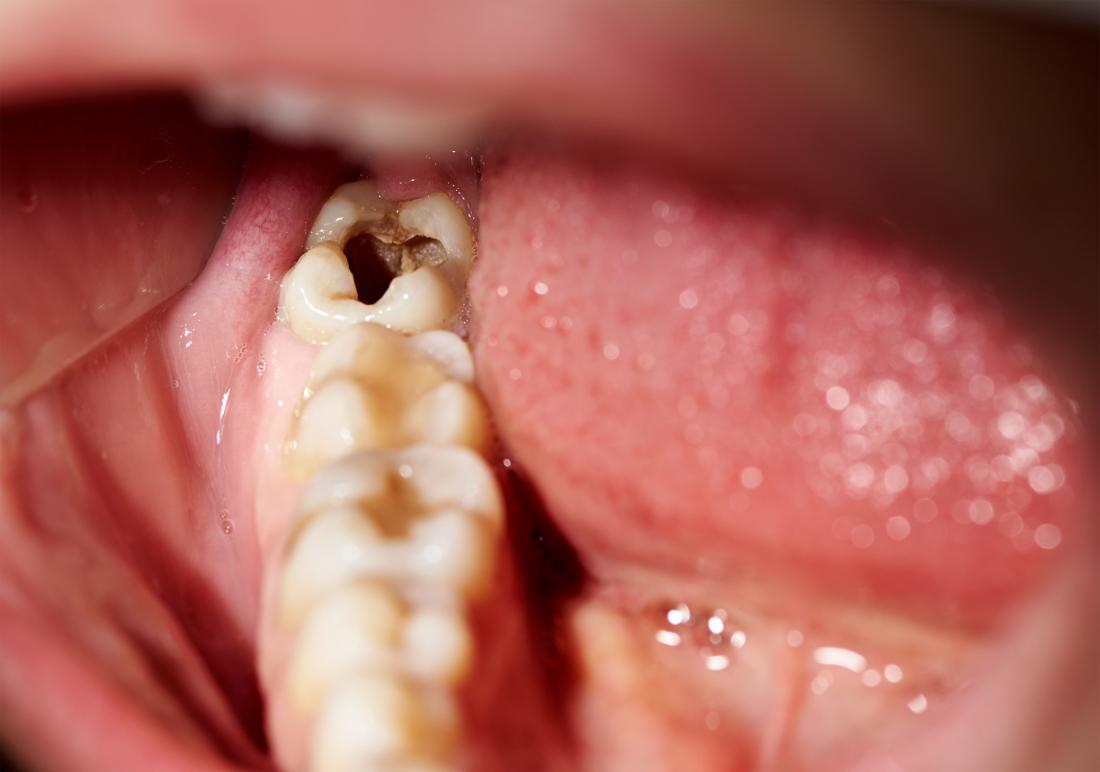

However, if a wisdom tooth is painful, misaligned, or leads to oral health issues, your dentist may recommend early extraction to prevent complications.

If a wisdom tooth grows in straight and doesn’t cause any issues, it can be left alone. However, in most cases, dentists recommend extraction due to potential complications, including: